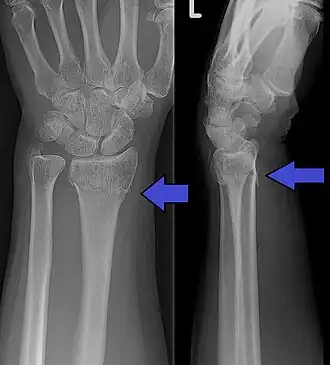

| Fratura de Colles no raio-X. | |

A fratura de Colles é a fratura da extremidade distal do rádio, onde o fragmento se desloca para trás e para o exterior.

A causa mais comum é uma queda leve sobre a mão espalmada, onde a extremidade distal do rádio sofre o impacto, e o fragmento ósseo se desloca posteriormente e lateralmente.

Tem como característica o aspecto da mão como o dorso de um garfo.

O principal diagnóstico é feito pelo raio-X (radiografia).